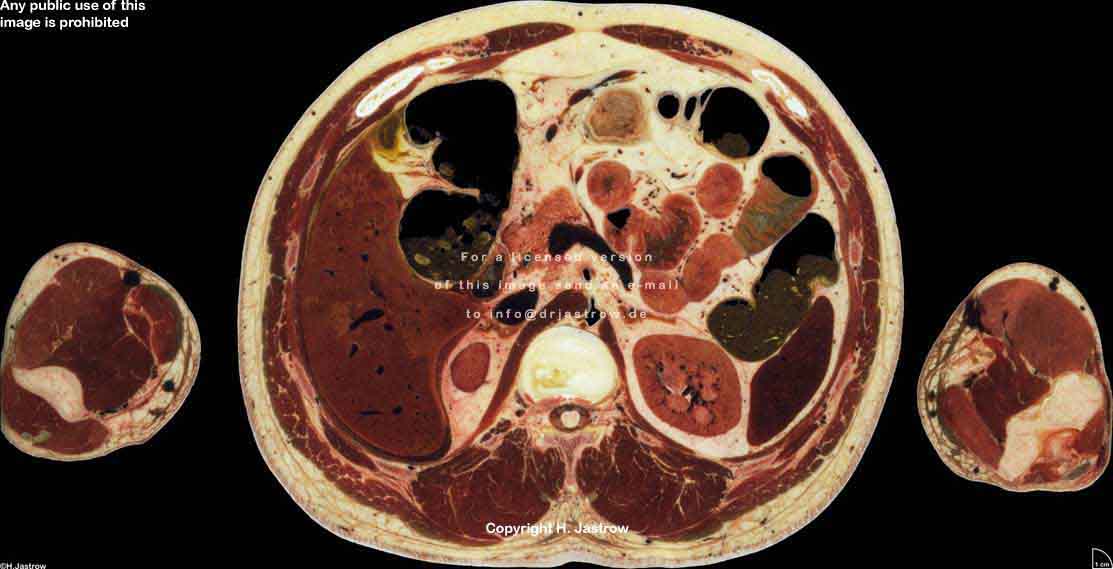

Visible Human male: Sectio transversalis 1579

CT

NMR

Pd                          / T2 \                         T1